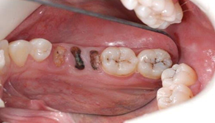

Retained Dental roots

After crown fracture there is only root present in oral cavity, which required extraction.

દાંતના મૂળિયા

જ્યારે દાંતનો ચાવવાનો ઉપયોગી ભાગ સડી ને કે અન્ય કારણોસર તૂટી ગયો ગયો અને ખાલી મૂળિયા રહ્યા હોય.